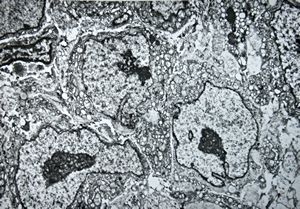

F, 48y. | lupus erythematodes … multiplicated vascular basement membrane

F, 48y. | lupus erythematodes … multiplicated vascular basement membrane

F, 48y. | lupus erythematodes … multiplicated vascular basement membrane